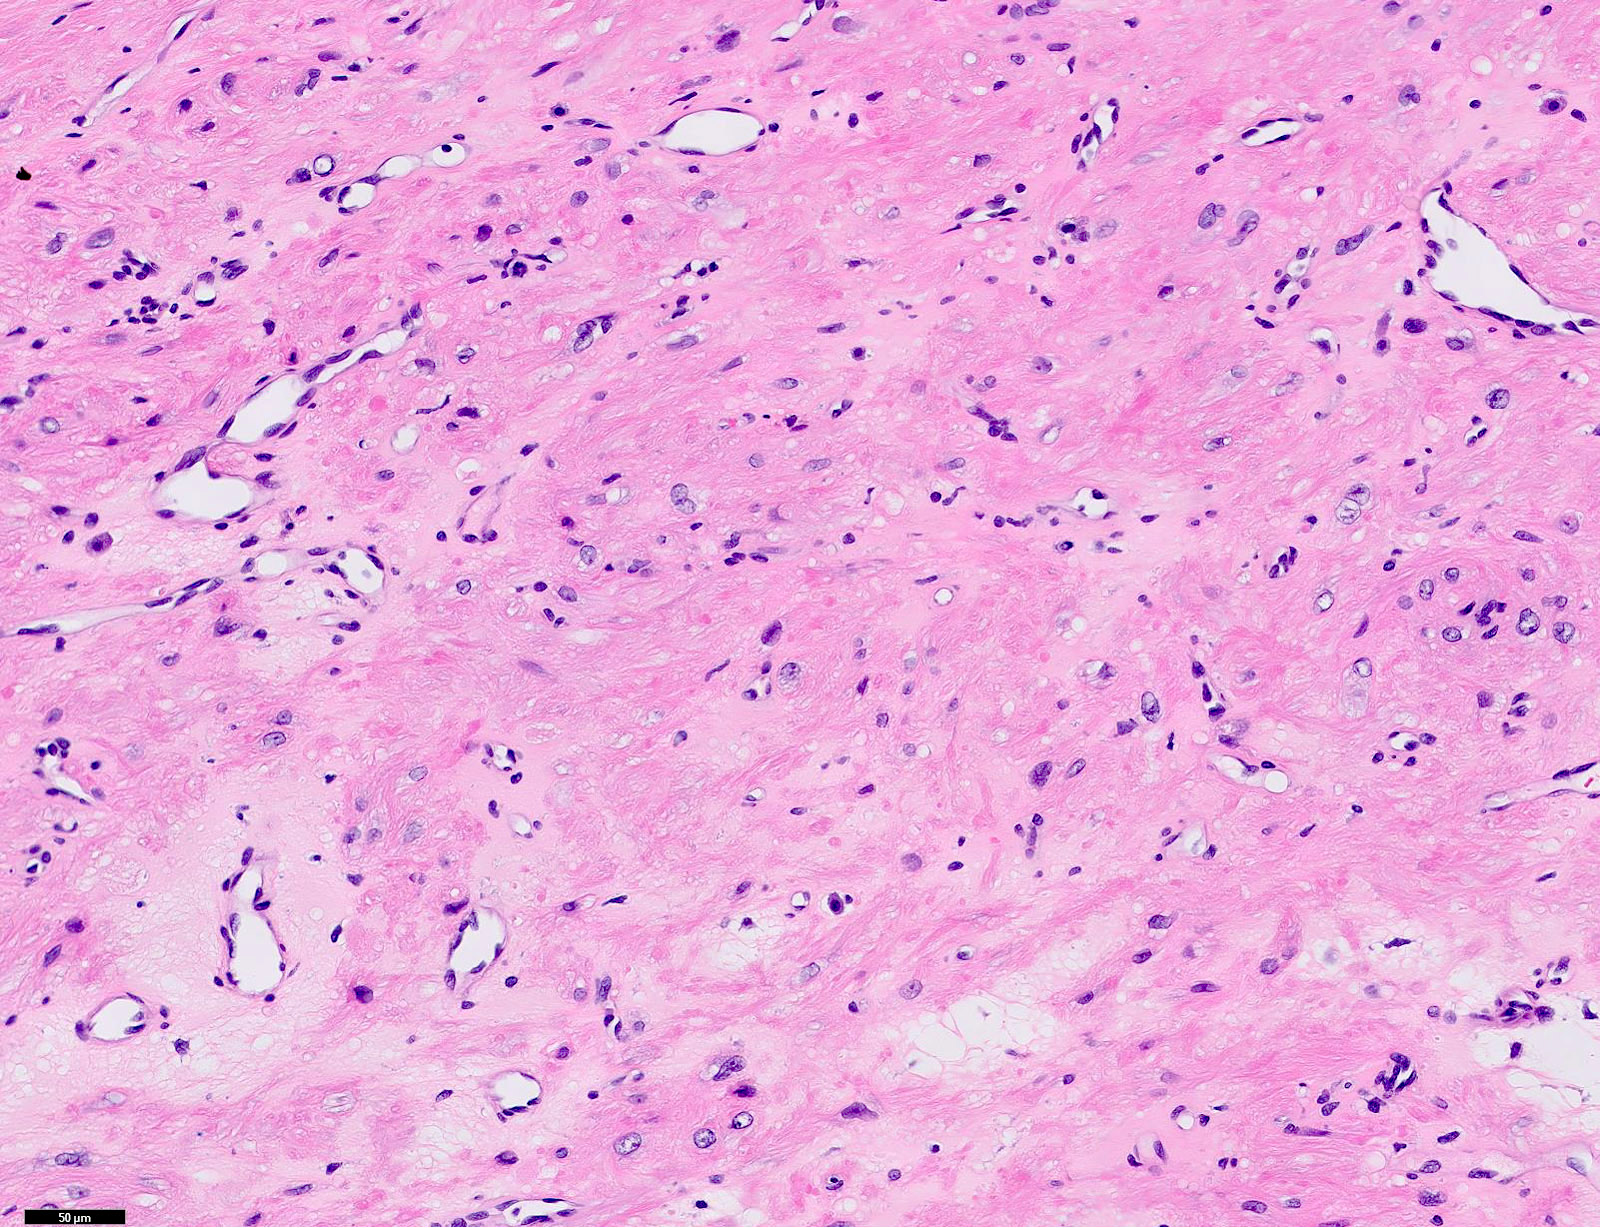

Microscopic (histologic) description

- Encapsulated proliferation of eosinophilic smooth muscle cells with minimal nuclear pleomorphism

- Rounded or slit-like veins with muscular walls present within the tumor (J Cutan Pathol 2017;44:342)

- Tumors can further be classified into 3 subcategories, first described by Morimoto et al:

- Solid type: smooth muscle bundles surround numerous small slit-like channels

- Venous type: thick walled vessels that are easily distinguished from the intervascular smooth muscle

- Calcification and marked degeneration, including hyalinization and myxoid changes, may be present (J Cutan Pathol 2017;44:342, J Ultrasound Med 2019;38:1201)

- Fat can be seen in a few cases; not to be mistaken for angiomyolipoma (Cancer 1984;54:126)

Microscopic (histologic) images

Contributed by Ohoud Aljarbou, M.D., Jijgee Munkhdelger, M.D., Ph.D. and Andrey Bychkov, M.D., Ph.D.

A. Angioleiomyoma. A mixture of smooth muscle bundles arranged in small fascicles and intervening vascular channels is noted. The concentric perivascular spindle cell proliferation which is characteristic for myopericytoma is absent. There are no glomus cells seen. Adipocytes are not seen in this image, which makes angiomyolipoma less likely.